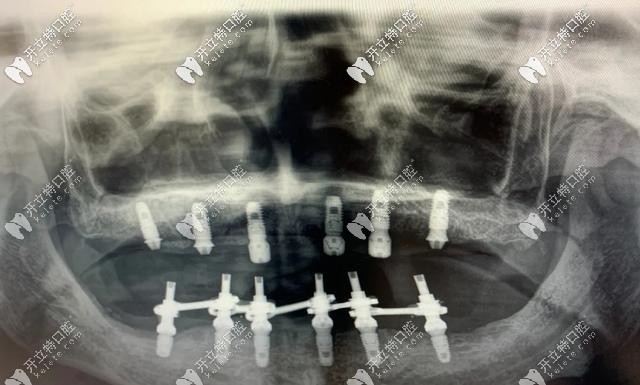

即刻負重種植牙主要針對全口無牙頜或半口無牙的情況下,每個半頜4-6顆種植牙就可以恢復(fù)半口的牙齒,術(shù)后2個小時即可戴牙進食,實現(xiàn)了當(dāng)天種當(dāng)天用。

即刻負重種植牙對骨質(zhì)要求比較高,牙槽骨骨量得充足,種植體長度大于10mm,直徑大于3.5mm,一般單顆牙缺失不適合即刻負重,適用于口內(nèi)多顆或全部牙齒缺失的人群。